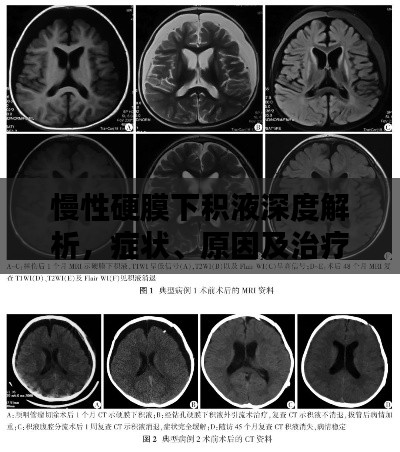

慢性硬膜下积液深度解析,症状、原因及治疗方法

在医学领域中,慢性硬膜下积液是一个相对常见的病症,本文将通过百度搜索,为您详细解析这一病症的相关知识。慢性硬膜下积液概述慢性硬膜下积液是指在硬脑膜下腔出现液体聚集的现象,这种病症通常表现为头痛、恶心、呕吐等症状,慢性...